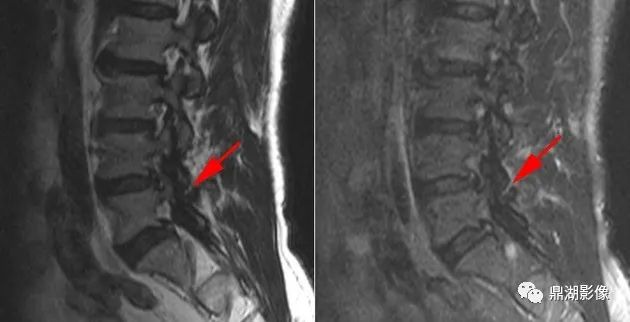

男性患者,40岁,腰背部疼痛,否认外伤史。

奥本海默小骨(Oppenheimer ossicle)

影像学特征:奥本海默小骨具有光整的骨皮质,相邻小关节的滑膜囊可与奥本海默小骨与关节突之间的裂隙相通。

在影像学上,需与关节突骨折相鉴别:奥本海默小骨形态规则、骨皮质光整、连续。